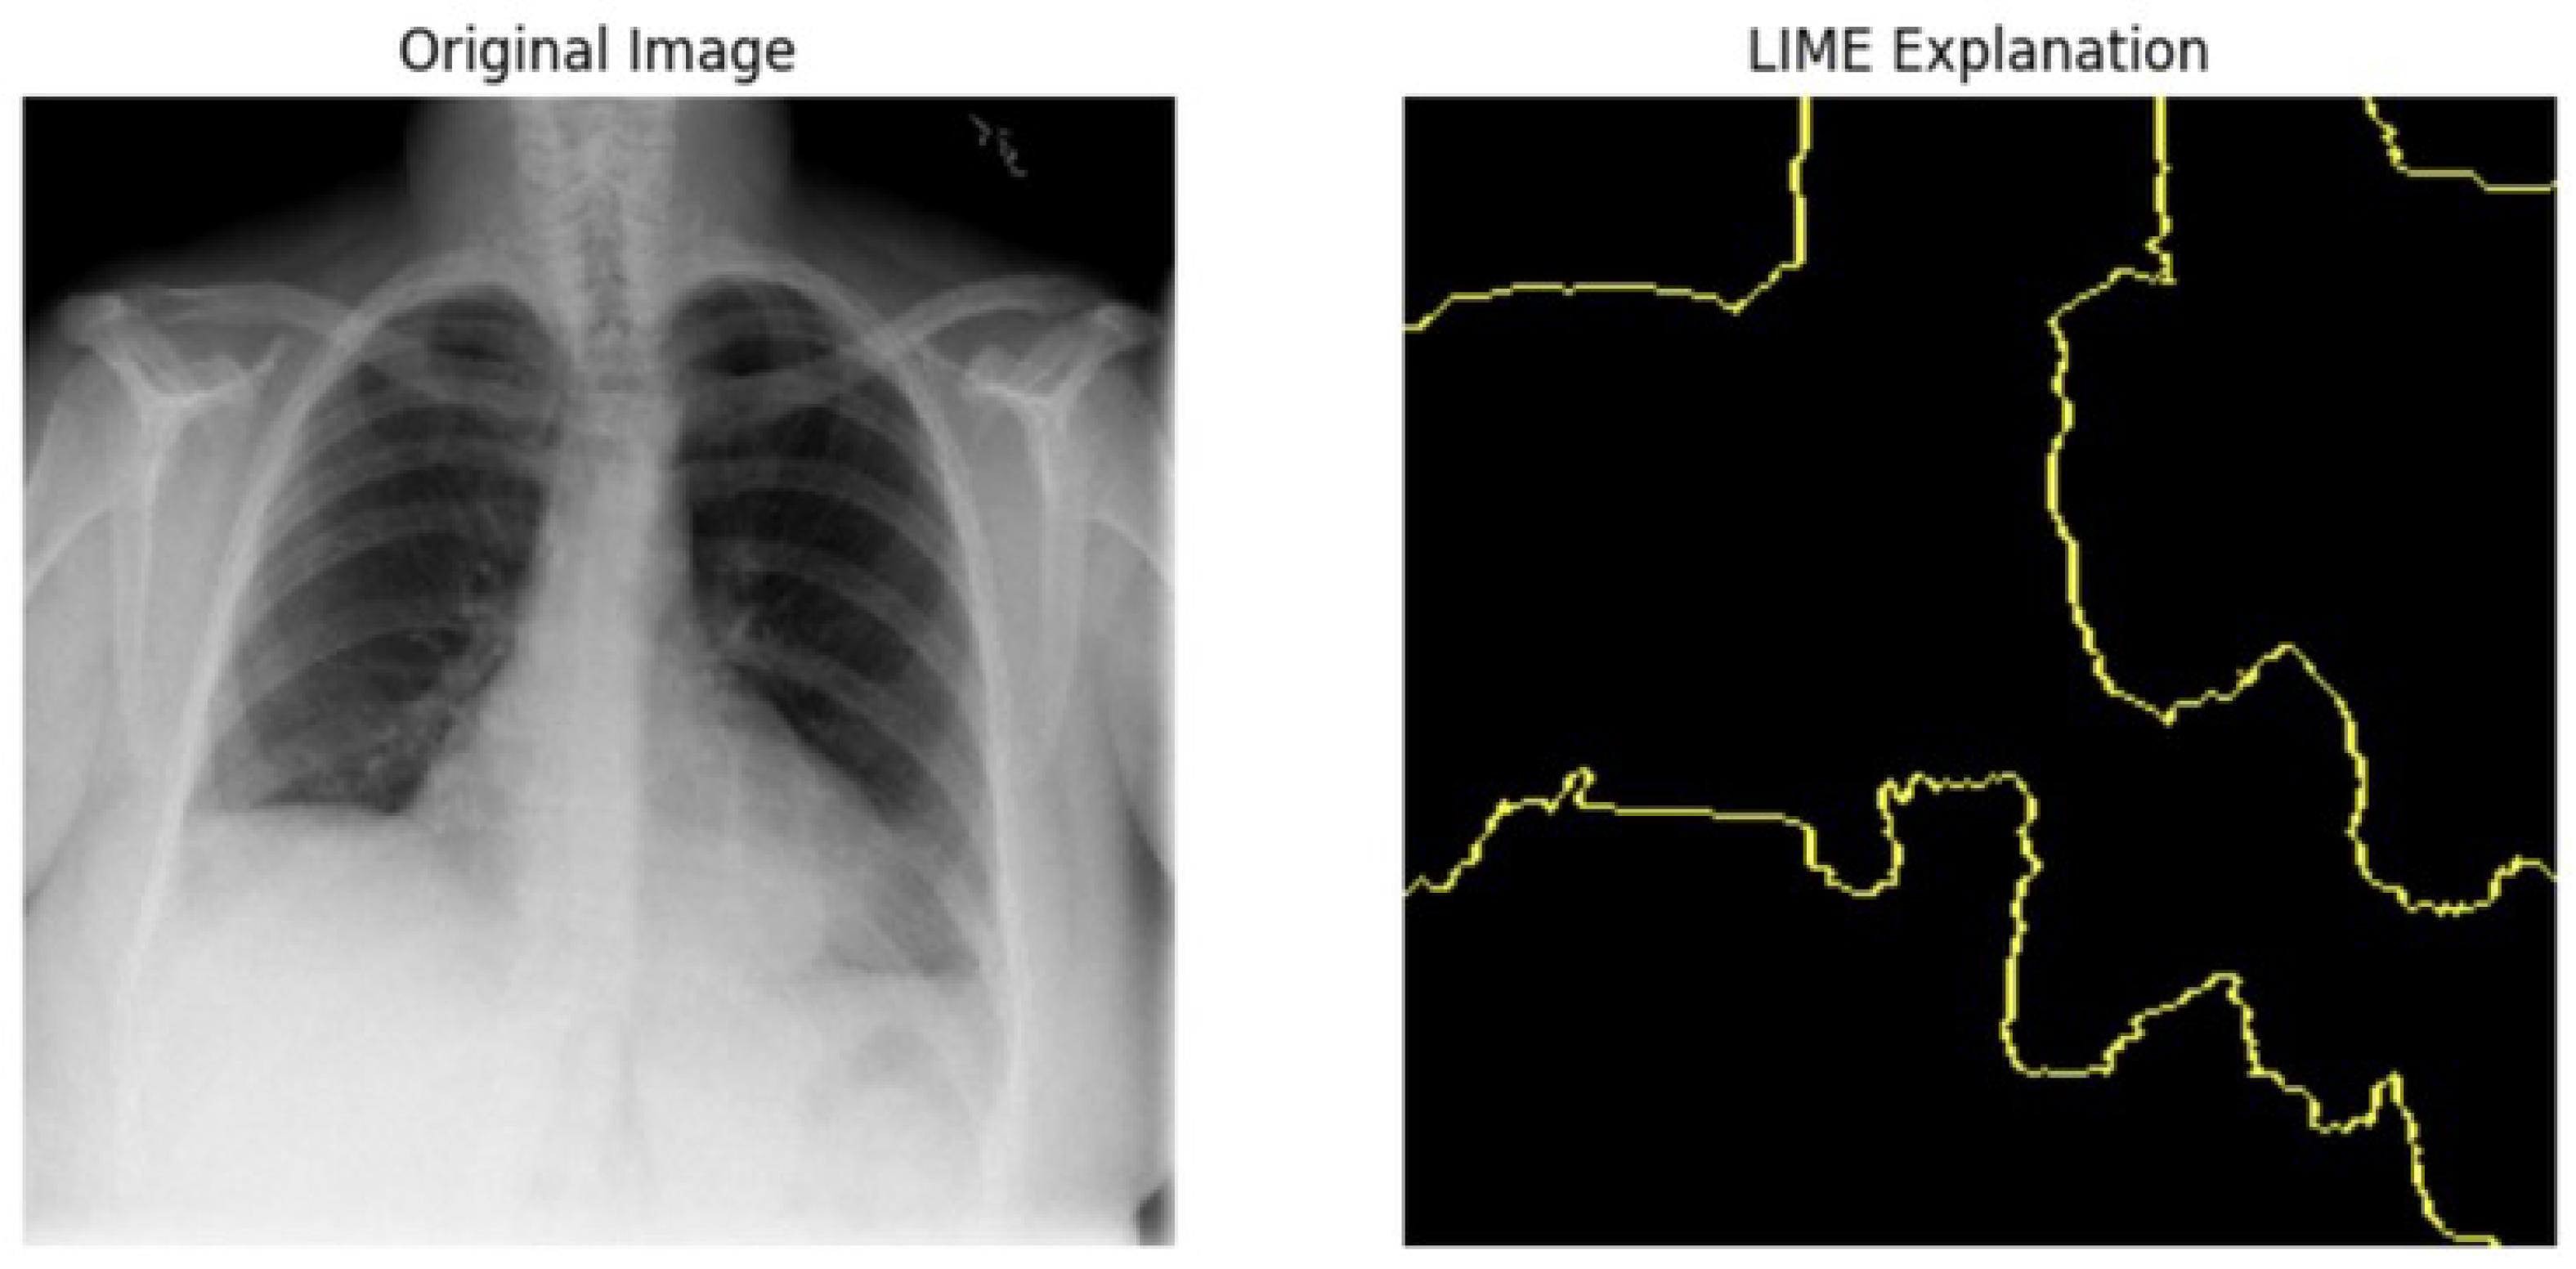

5.4.1. Local Interpretable Model-Agnostic Explanations for Clinical Validation

We applied scientific analysis on a random 7 sample, which was provided by the clinical specialist. The LIME Analysis for Image Data (a), (b), (c), (d), (e), and (f) is in Figure 22, Figure 23, Figure 24, Figure 25, Figure 26 and Figure 27. There are two parts of LIME analysis from the provided chest X-ray images to detect the disease area. Original Image and LIME explanation;

• Original Image: The patient’s thoracic cavity. It displays the typical anatomical structures of the chest, including the lungs, ribs, and heart.

• LIME Explanation: The result of applying LIME to the chest X-ray image. The yellow boundaries indicate the regions of the image that were most influential in the model’s decision-making process when determining whether the image indicated a particular condition. In this context, these regions are the parts of the X-ray that the AI model considered most important for making its diagnostic prediction.

The analysis very useful for clinicians to understand the model’s behavior and ensure that it aligns with medical expertise. The use of LIME helps in making the AI model’s interpretability decisions more transparent and interpretable. It allows medical professionals to verify whether the AI’s focus areas correspond to clinically significant regions. It also enhanced diagnostic capability of understanding which parts of the images in the AI model in refining the model further and ensures that it makes accurate and reliable predictions. This is particularly crucial in medical diagnostics where interpretability and accuracy are paramount.

Figure 26. LIME Analysis for Image Data (e) on original image to LIME explanation.

Jpm 14 00856 g026